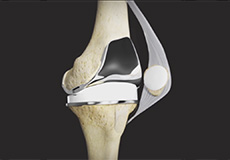

ACL Preserving Total Knee Replacement

ACL preserving total knee replacement is an advanced surgery performed to replace a damaged knee joint with a prosthesis while preserving the anterior cruciate ligament (ACL). The ACL is a very important ligament that runs diagonally across the front of the knee and provides rotational knee stability.